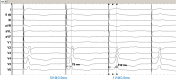

Conduction system pacing (CSP) has emerged as a more physiological alternative to right ventricular pacing and is also being used in selected cases for cardiac resynchronization therapy. His bundle pacing was first introduced over two decades ago and its use has risen over the last five years with the advent of tools which have facilitated implantation. Left bundle branch area pacing is more recent but its adoption is growing fast due to a wider target area and excellent electrical parameters. Nevertheless, as with any intervention, proper technique is a prerequisite for safe and effective delivery of therapy. This document aims to standardize the procedure and to provide a framework for physicians who wish to start CSP implantation, or who wish to improve their technique.